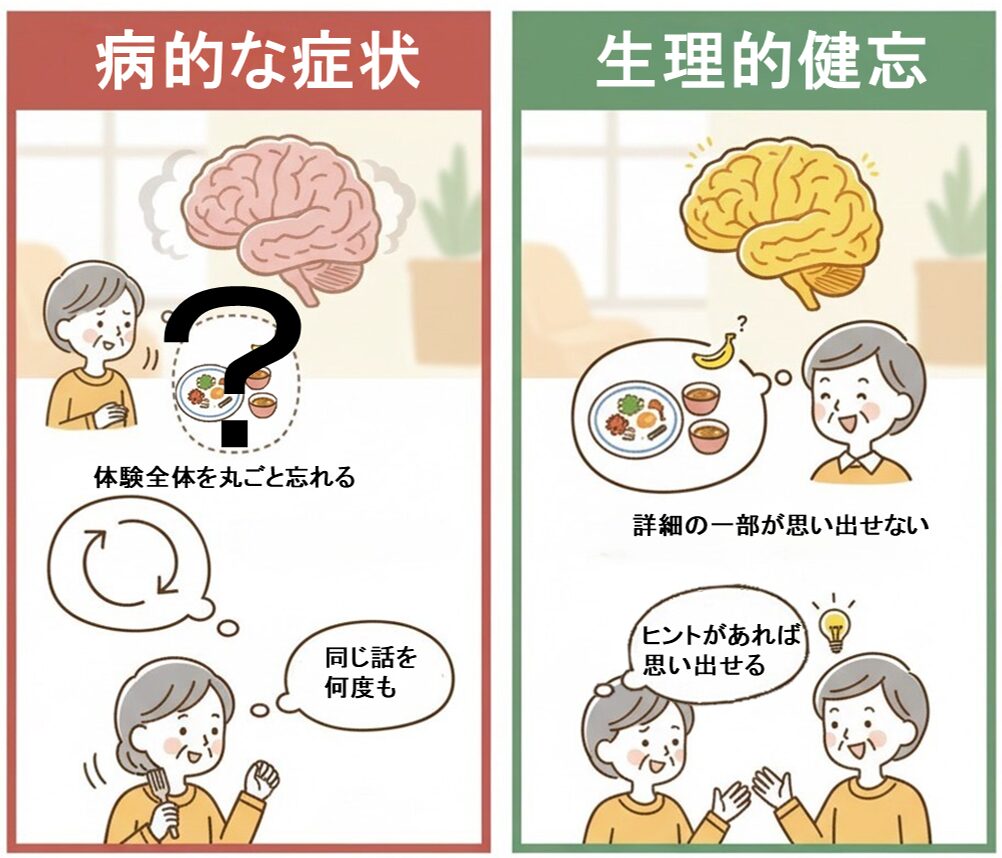

脳萎縮の初期には、非常に微妙で「年のせいかな」と見過ごされがちな変化が現れます。特に注意すべきは、加齢による自然な「生理的健忘」との決定的な違いです。

病的な初期サイン:体験が「すっぽり抜ける」ことの危険性

脳の萎縮に伴う病的なサインは、単なる加齢による物忘れと異なり、体験が丸ごと記憶から抜け落ちるのが特徴です。

| 記憶 | 体験全体(例:昨日誰と会ったか、朝食を食べたか)を丸ごと忘れる | 詳細の一部(例:朝食の献立、友人の名前)が思い出せない |

| 反復 | 同じ話や質問を何度も繰り返し、指摘されても自覚がない | 話をしようとして言葉に詰まるが、ヒントがあれば思い出せる |

| 感情・意欲 | 以前は活動的だった人が無気力になる、あるいは怒りっぽくなる | 趣味や関心は維持できている |

このような症状は、単なる年齢のせいではなく脳萎縮の初期症状である可能性があります。